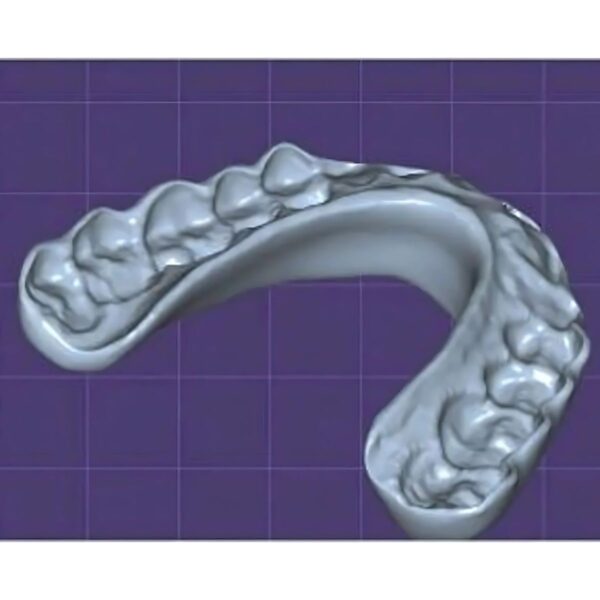

China Dental Design Complex Case Gallery

Challenging Projects That Showcase Our China Dental Design Expertise

Dental Aigners

Advanced China Dental Design Capabilities

Our expert China Dental Design team delivers precision, quality, and cost-effectiveness for every complex restoration project